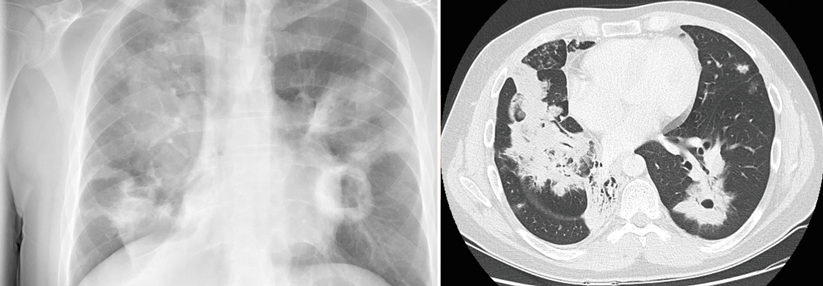

Bildgebung

Thorax-Röntgen

• Kleine retroklavikuläre Infiltrate oft nicht erkennbar (besser CT)

• Bei Verdacht auf frische Infektion Kontrollaufnahme frühestens nach 3 Monaten